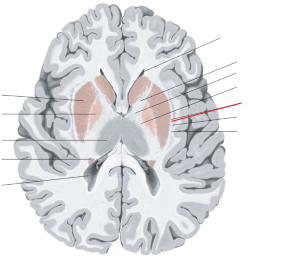

nucleus caudatus

putamen

globus pallidus

capsula interna (corona radiata)

capsula externa

capsula extrema

hippocampus

amygdala

fornix

laterale ventrikels (I en II)